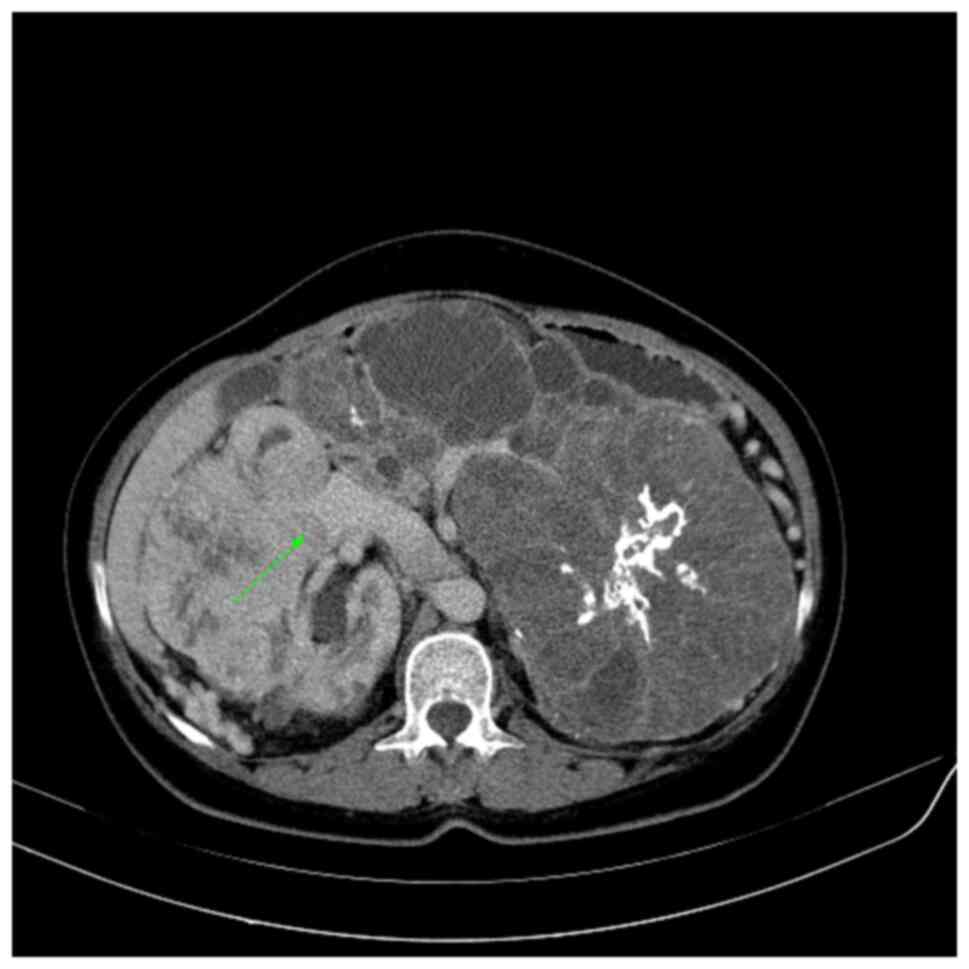

Fig. 2 demonstrates one of the criteria for perinephric fat invasion, namely, a nodular extension from the tumor to the perinephric fat (T3a). Fig. 3 shows an enhanced filling defect in the right main renal vein in the arterial and nephrographic phases without extension to the IVC.

Figure 2

Perinephric fat invasion. Right-sided renal cell carcinoma with an enhancing nodule from the anterior part of the tumor invading the perinephric fat (stage T3a), as indicated by the arrow.

The involvement of perinephric fat tissue is a critical element in therapeutic planning. In fact, perirenal fat tissue infiltration alters the surgical technique from conservative to radical nephrectomy (13). One of the most challenging aspects of staging renal tumors is detecting perinephric fat invasion, which causes tumors of any size to be classified as T3a. Catalano et al (13) demonstrated perinephric fat invasion with a sensitivity and specificity of ~96 and 93%, respectively. El-Hefnawy et al (17) observed a specificity of 80%, while Sokhi et al (10) reported a sensitivity and specificity of 83 and 76%, respectively. Liu et al (18) showed a sensitivity and specificity of 32 and 86%, respectively. The current study found a sensitivity and specificity of 80 and 95%, respectively, which was somewhat higher than previous studies. These values depend on the criteria for perinephric fat invasion, which varied among the studies. In the present study, perinephric fat stranding was considered as perinephric fat invasion in addition to other features, such as perinephric nodules, an irregular tumor edge and angular lobulation.